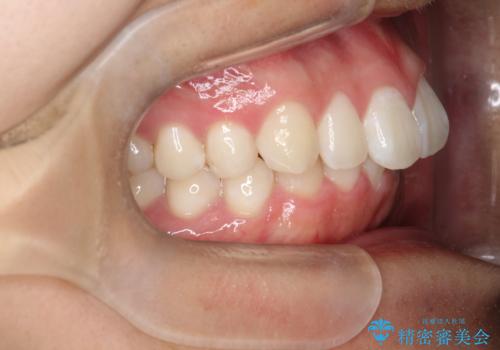

- 歯のデコボコと過蓋咬合を主訴に来院された患者様です。

アーチの拡大とIPRを行い非抜歯で治療を行いました。

歯を抜かずに叢生(デコボコ歯列)と過蓋咬合を改善する事が出来ました。

インビザラインによる治療でも十分に美しい歯並びを実現でき、患者様にも大変ご満足いただけました。